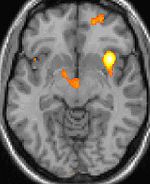

The most important step in diagnosing a headache is for the physician to take a careful history and to examine the patient. In the majority of cases the diagnosis will be a "primary headache" which means that the headache, whilst unpleasant is not an occurring as a manifestation of a more serious condition. The main types of primary headache are tension headache, migraine and the trigeminal autonomic cephalalgias of which cluster headache is an example. As it is often difficult for patients to recall the precise details regarding each headache, it is often useful for the sufferer to fill-out a "headache diary" detailing the characteristics of the headache. When the headache does not clearly fit into one of the recognized primary headache syndromes or when atypical symptoms or signs are present then further investigations are justified. Computed tomography (CT/CAT) scans of the brain or sinuses are commonly performed, or magnetic resonance imaging (MRI) in specific settings. Blood tests may help narrow down the differential diagnosis, but are rarely confirmatory of specific headache forms.